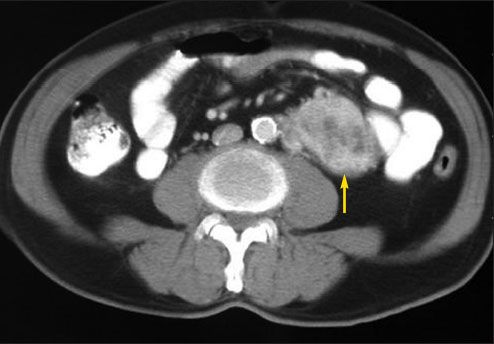

On admission, his blood pressure was 220/100 mm Hg. He had right upper quadrant tenderness. An ultrasonogram and CT scan of the abdomen revealed acute cholecystitis with stones in the common duct and an incidental 5 x 6-cm left para-aortic mass (Figure 1). The patient underwent endoscopic retrograde cholangiopancreatography, during which his systolic blood pressure was difficult to control and fluctuated widely.

Figure 1 – A CT scan of the abdomen with oral contrast indicated a para-aortic mass (yellow arrow).